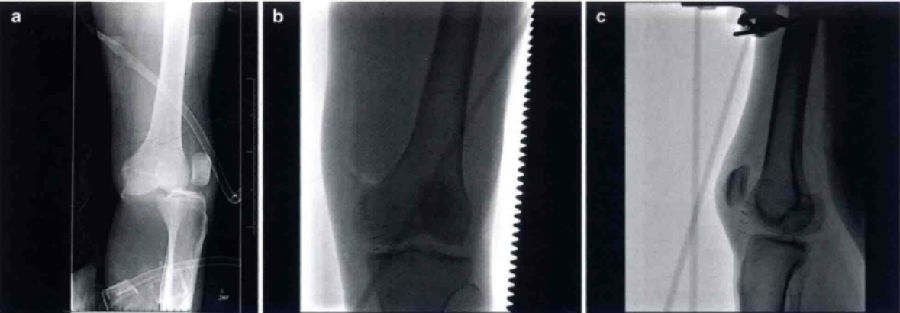

初步评估应涵盖全而的体格检查。因为膝关节脱位经常发生于多发性创伤的患者,体格检查应当包含对患者头部、胸部、腹部和四肢的一般评估。初步检查应包括检查膝关节贯穿伤口、存在的畸形以及膝关节活动度的检查。检查制带时必须包括屈膝20°时Lachman检查、屈膝90°时前后抽屉试验、屈膝0°和30°时内外翻应力试验,以及如果患者能够耐受疼痛时需行Dial试验。对膝关节脱位的检查通过采取标准的Lachman试验(将检查者的大腿置于被检者的膝关节下)通常可以减少疼痛以及提高准确性。触诊通常用于检查伸膝装置或䐃绳肌腱断裂。如患者可进行直腿抬高动作,对于伸膝装置的情况检查十分有用。另外,应仔细检查血管的解剖情况,这对于膝关节脱位的治疗方式起到决定性的作用。如果血管损害被延迟诊断,可导致骨筋膜室综合征甚至截肢。最简易的血管检查包括触诊胫后和足背动脉搏动以及毛细血管充盈时间的触诊。基于初步评估,进一步的检查应当根据循证指南进行,包括ABI指数、血管造影、血管CT造影和腘动脉紧急探查。血管治疗的必要性取决于检查的结果(图1),而神经功能检查评估对于无意识的患者或有多发创伤存在的患者十分困难,对于胫神经和腓总神经的评估十分重要,需要尽量进行。术前神经损伤的诊断可以帮助制订治疗计划和预测结果。

图1 膝关节脱位导致腘动脉损伤的血管造影图像